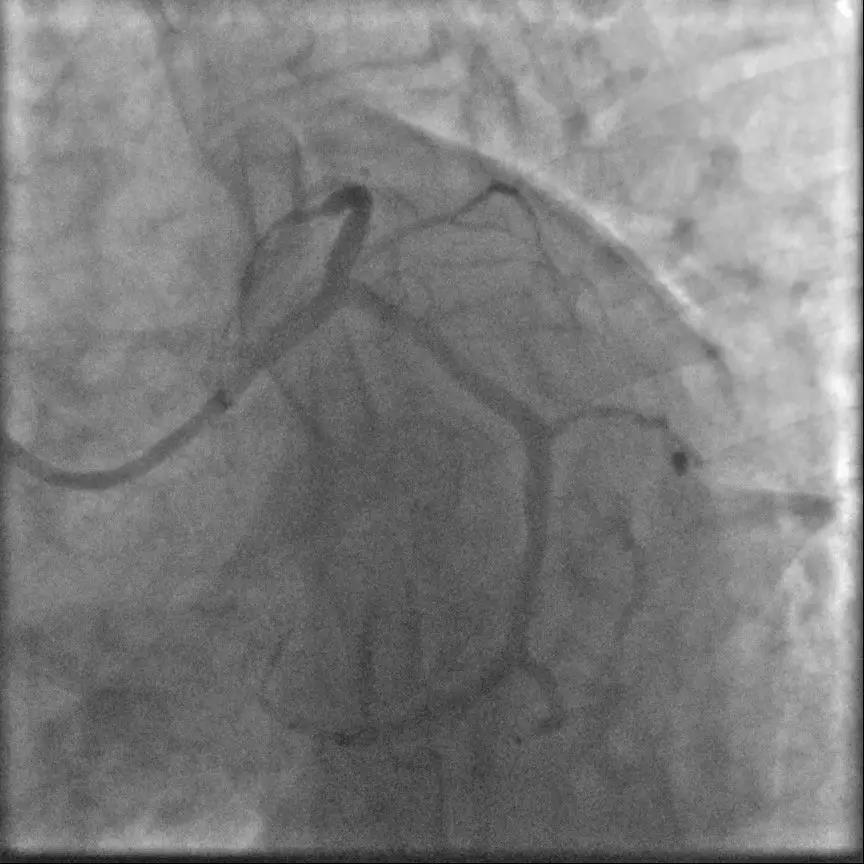

术后